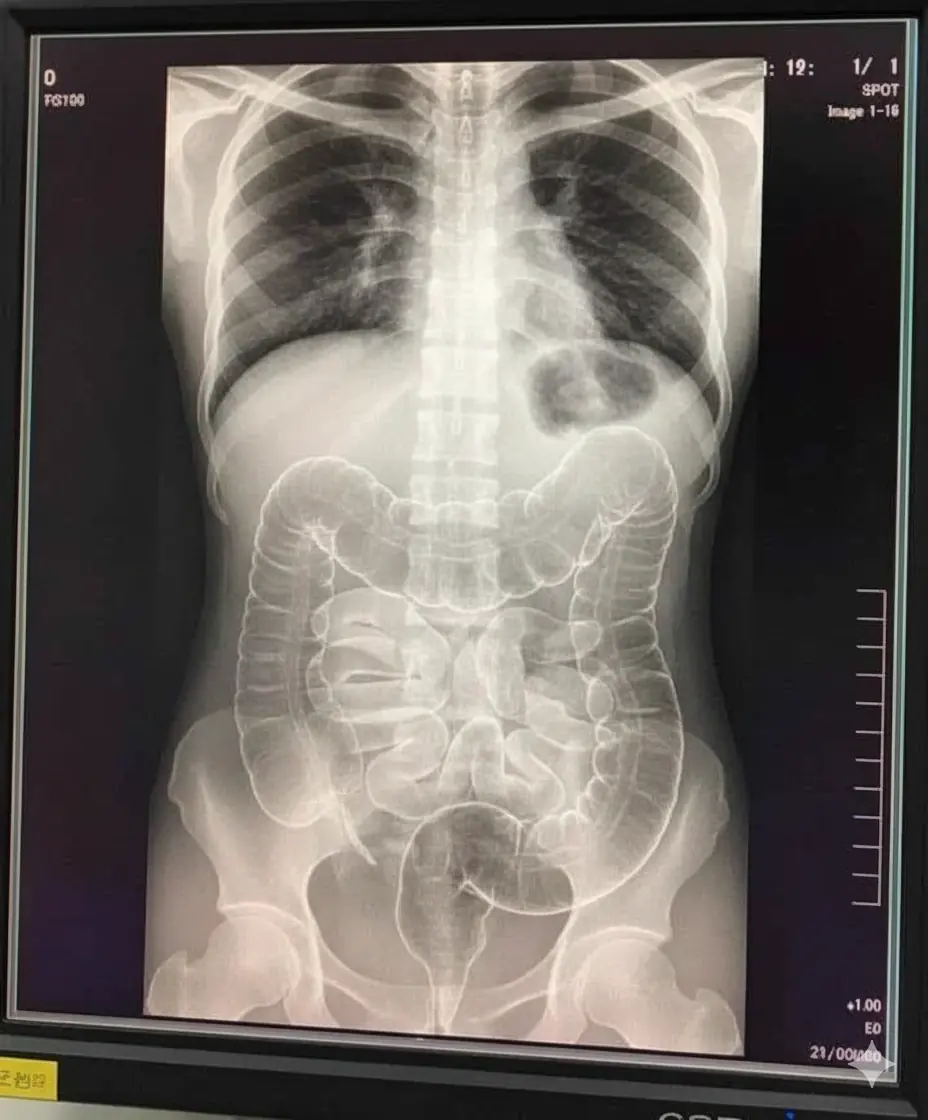

When she finally visited the hospital, doctors immediately ordered diagnostic imaging. What the X-ray revealed shocked both the medical staff and the young woman.

Her intestines were packed with hardened stool, filling large sections of the colon and causing visible distention. The accumulation was not mild, nor was it typical — it was a severe case resembling a full bowel obstruction.

What the X-ray showed:

Intense compaction of stool throughout the large intestine

A colon stretched beyond normal size

Very limited space for normal movement of intestinal contents

Signs that the condition had been present far longer than she realized

It was a striking, almost alarming image - one that clearly illustrated how severe constipation can become when left unaddressed.

Doctors explained that this was not simply “being backed up.” Her colon was under significant strain, and if ignored, the situation could have led to bowel perforation, infection, or other life-threatening complications.